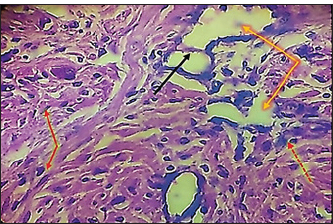

In the surgical group (GII), the main characteristic findings at 30 days post-surgery were degeneration of seminiferous tubules, multinucleated spermatid, infiltration of inflammatory cells, atrophy of Leydig cells, and vacuole degeneration of basal and Sertoli epithelium (Fig. 8). Furthermore, there was loss of the straight shape of the tubuli recti, disequimentaion of the tubuli recti epithelium, and proliferation of myoid cells (Fig. 9). Other sections showed coagulative necrosis and ghost tubules in the rete testis (Figs. 10 and 11).

Fig. 8. Histopathological section of testes from dogs in the surgical group at 30 days post-surgery, showing degeneration of seminferous tubules (red dotted arrow), multinucleated spermatid (yellow arrows), infiltration of inflammatory cells (red arrow), atrophy of Leydig cells (black arrow), and vacuole degeneration of basel and sertoli epithelium (black dotted arrow) (H & E stain 10X).

In the surgical group (GII), the main characteristic findings at 30 days post-surgery were degeneration of seminiferous tubules, multinucleated spermatid, infiltration of inflammatory cells, atrophy of Leydig cells, and vacuole degeneration of basal and Sertoli epithelium. Furthermore, the tubuli recti lose their straight shape, the tubuli recti epithelium disequilibrates, and myoid cells proliferate. The other section showed coagulative necrosis and ghost tubules in the rete testis. This hardly changes in testicular tissue, which may be due to ischemia resulting from ligation of the testicular blood supply, as explained by (González and Ciancio, 2015; Spaska et al., 2024).